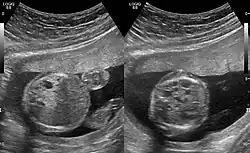

CPAMs are classified into three different types based largely on their gross appearance. Type I has a large (>2 cm) multiloculated cysts. Type II has smaller uniform cysts. Type III is not grossly cystic, referred to as the "adenomatoid" type. Microscopically, the lesions are not true cysts, but communicate with the surrounding parenchyma. Some lesions have an abnormal connection to a blood vessel from an aorta and are referred to as "hybrid lesions."

The earliest point at which a CPAM can be detected is by prenatal ultrasound. The classic description is of an echogenic lung mass that gradually disappears over subsequent ultrasounds. The disappearance is due to the malformation becoming filled with fluid over the course of the gestation, allowing the ultrasound waves to penetrate it more easily and rendering it invisible on sonographic imaging. When a CPAM is rapidly growing, either solid or with a dominant cyst, they have a higher incidence of developing venous outflow obstruction, cardiac failure and ultimately hydrops fetalis. If hydrops is not present, the fetus has a 95% chance of survival. When hydrops is present, risk of fetal demise is much greater without in utero surgery to correct the pathophysiology. The greatest period of growth is during the end of the second trimester, between 20 and 26 weeks.

A measure of mass volume divided by head circumference, termed cystic adenomatoid malformation volume ratio (CVR) has been developed to predict the risk of hydrops. The lung mass volume is determined using the formula (length × width × anteroposterior diameter ÷ 2), divided by head circumference. With a CVR greater than 1.6 being considered high risk. Fetuses with a CVR less than 1.6 and without a dominant cyst have less than a 3% risk of hydrops. After delivery, if the patient is symptomatic, resection is mandated. If the infant is asymptomatic, the need for resection is a subject of debate, though it is usually recommended. Development of recurrent infections, rhabdomyosarcoma, adenocarcinomas in situ within the lung malformation have been reported.[4]